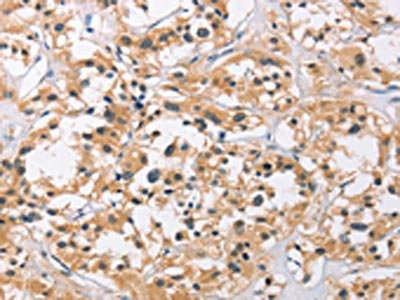

The image on the left is immunohistochemistry of paraffin-embedded Human thyroid cancer tissue using CSB-PA251074(C3AR1 Antibody) at dilution 1/50, on the right is treated with fusion protein. (Original magnification: ×200)

The image on the left is immunohistochemistry of paraffin-embedded Human brain tissue using CSB-PA251074(C3AR1 Antibody) at dilution 1/50, on the right is treated with fusion protein. (Original magnification: ×200)